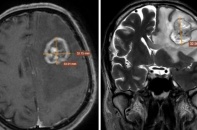

Một khối u bất thường ở vùng ngực tưởng chừng chỉ là tổn thương tại chỗ, nhưng lại trở thành dấu hiệu cảnh báo một bệnh lý ác tính phức tạp - ung thư biểu mô tế bào gan di căn thành ngực.